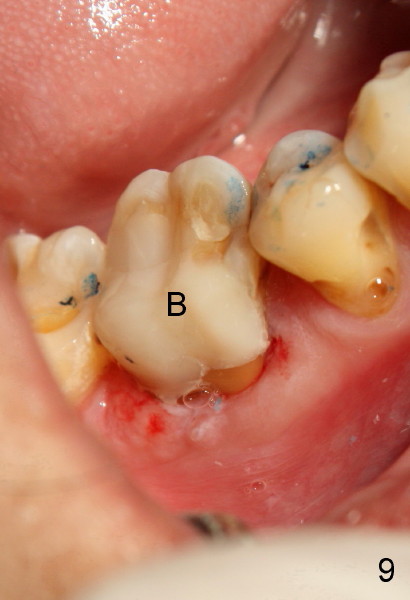

To further improve visibility, the arm of rubber dam clamp is changed from distal to mesial aspect of #30 (compare R in Fig.6 and 7). DL orifice is finally found, close to DB one. The DL canal is obliterated. It is debrided until #20 hand file short of WL. Fig.7 shows the chamber after RCT with gutta percha. * indicates thin pulpal floor. Fig.8 and 9 are taken after build-up (B). It appears that distal canals are divergent apically and that there are most likely two distal roots.